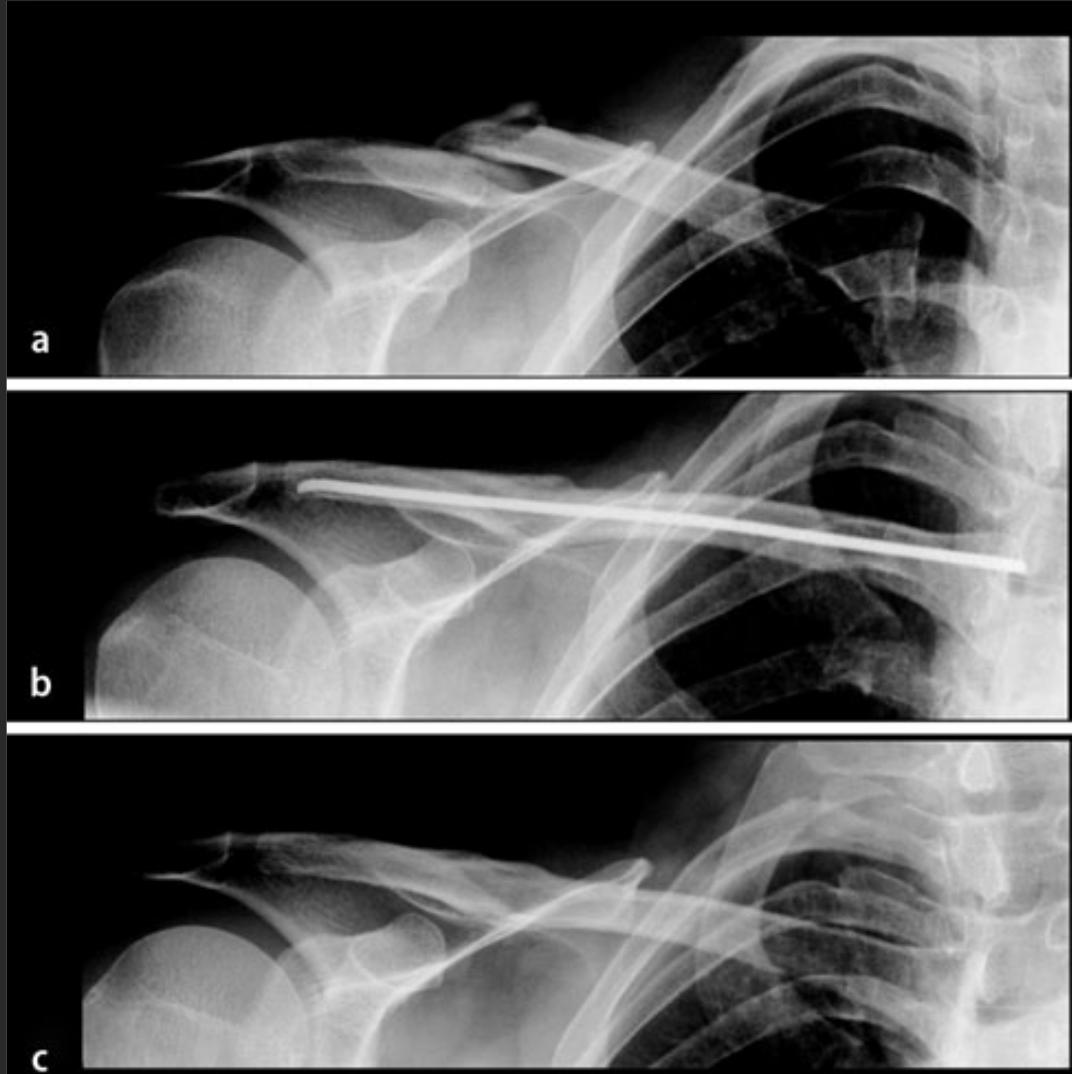

手术髓内固定方式

锁骨骨折吃什么食物最好,锁骨骨折怎么绑绷带视频

手术钢板螺钉内固定

根据病情,采取合适的治疗方式,使孩子最大程度受益。